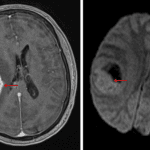

- Large, peripherally-enhancing, centrally necrotic mass bridging the right frontal and parietal lobes measuring 4.5 x 4.2 x 4.5 cm with extensive T2/FLAIR signal hyperintensity in the surrounding white matter

- Restricted diffusion correlating with the enhancing components

- Susceptibility artifact correlating with the area of central necrosis

- Additionally masslike area of restricted diffusion in the posterior left temporal lobe with a corresponding focus of enhancement along its anterior margin

- Mass effect in the right cerebral hemisphere resulting in local sulcal effacement, crowding of the right lateral ventricle, and 9 mm right-to-left midline shift

- Mild dilation of the temporal horn of the right lateral ventricle concerning for entrapment